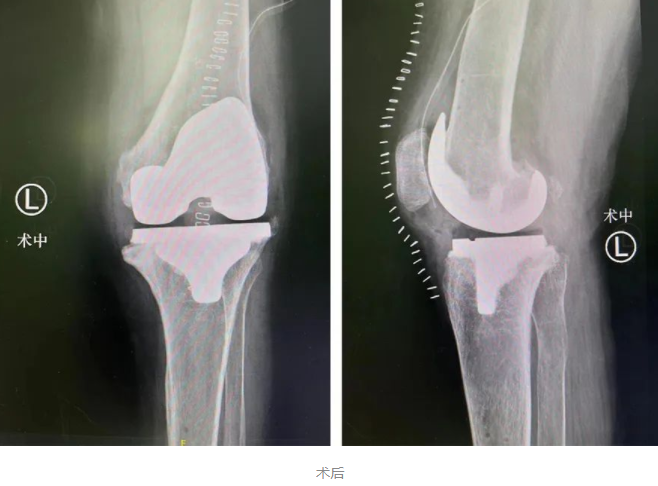

在结合相关资料及术前讨论后,sararz关节外科张传开、郝亮、王琳、蒋涛手术团队为李大姐在Mako关节置换机器人导航下行左侧人工膝关节置换术。

术前,Mako机器人基于CT进行3D的智能建模,根据患者实际情况个性化定制手术方案。同时,在术中实时根据患者具体软组织张力进行动态调整,辅助手术医生进行精准化、个性化的手术操作。尤其是对截骨、假体安装等重要环节,都进行了全程三维定位,实时将角度、大小、骨质覆盖等重要信息通过数字影像及时传达给手术医生,帮助医生做出准确判断,将手术精度控制在毫米级,完美实现了“精准手术”的要求。

术中在Mako机器人辅助下进行截骨,更精准、更安全

与传统骨科手术相比,Mako机器人能够辅助手术医生准确快速地完成假体植入,其精准度远超传统术式,解决了手术医生“看不准”、“拿不稳”的问题,同时在术后也使患者创伤更小、康复更快、关节功能更佳、假体生存率更长,生活质量大大提高。